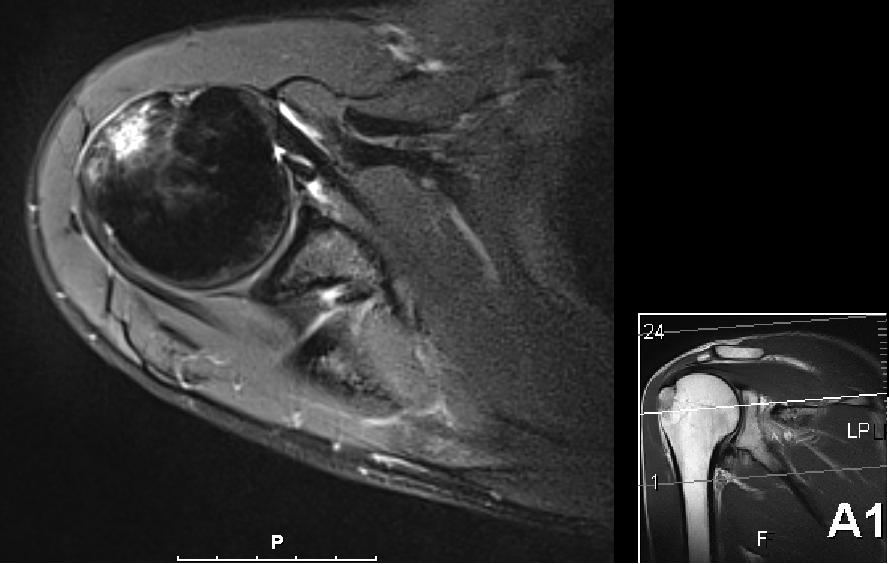

Heldigvis har det vært fremgang hele veien og det har blitt bedre hver dag. For 2 uker siden hadde jeg min første ”normale” svømmeøkt der jeg svømte crawl med begge armene. Det var noe sporadisk smerter forbundet med det, men veldig lite og 4000 meter med svømmeføtter (for å avlaste armene litt) gikk helt greit. Etter det har det blitt flere gode svømmeøkter der det har vært stor fremgang i den forferdelig rustne svømmeformen. Bare for å få bekreftet min mistanke om at det kun er noe mindre betennelse igjen og at det ikke var noe annet galt så fikk jeg dratt innom Aleris Oslo for en MR-undersøkelse. Dette var noe min kiropraktor Kristian og fysioterapeut Jørn Erik hos Klinikk for Alle ønsket hele veien men med ukependling til Stavanger og en veldig tettpakket plan før og etter Ironman Sør-Afrika så tok var drøye 5 uker etterpå det første jeg fikk til.

I forrige uke kom uansett svaret og resultatet var ikke akkurat helt som forventet. Nå var det riktig nok noe betennelse (aka bursitt) i skuldra som forventet men det var også et brudd i kanten på skuldra, såkalt tuberculum majos fracture på 2 x 2 cm. Så Kristian og Jørn Erik var rimelig overrasket over at jeg meldt tilbake at svømmingen gikk så bra.

Nå er det bare 6 dager til Ironman 70.3 Mallorca, og som alltid så ønsker jeg selvsagt å delta, men forstår at det kanskje ikke er det mest fornuftige. Om noen av dere har erfaringer eller gode råd/tips så tas de i mot med stor takk! Nå forstår jeg at radiolog er et eget yrke og tolking av MR-bilder krever mye erfaring og kunnskap, men jeg syntes ikke det ser såååå ille ut egentlig.

Skulderbilde